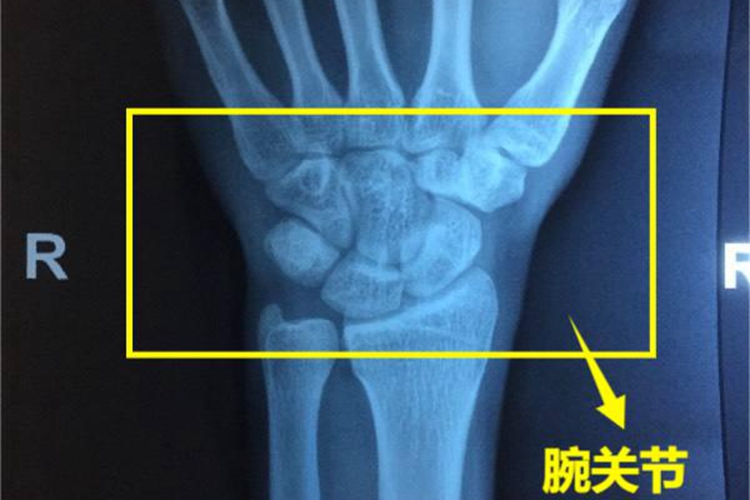

腕关节在手腕处,位于手掌和前臂之间,由15块骨及它们构成的20个关节面所组成。

腕关节位于手掌以上,前臂以下,可以灵活转动。腕关节有15块骨,包括桡骨、尺骨、8块腕骨以及5个掌骨基底部,及它们构成的20个关节面所组成。